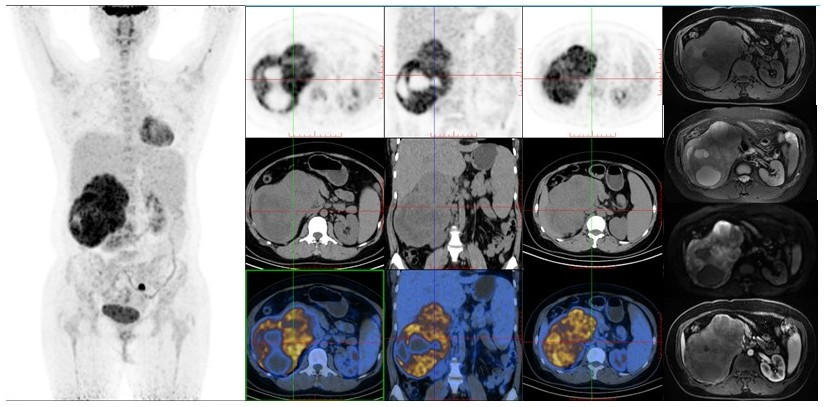

病例(3为一老年女性,右腹部疼痛就诊,CT提示右侧肾上腺囊实性占位MRI示占位T1WI混杂稍低信号、压脂T2WI混杂高信号、DWI高信号改变18F-FDG PET/CT示占位代谢轻度不均匀增高,占位周围稍大淋巴结伴代谢轻度增高肾上腺占位)穿刺病理为肾上腺皮质癌

病例3. 女,66岁,右腹部疼痛半月余肾上腺皮质癌